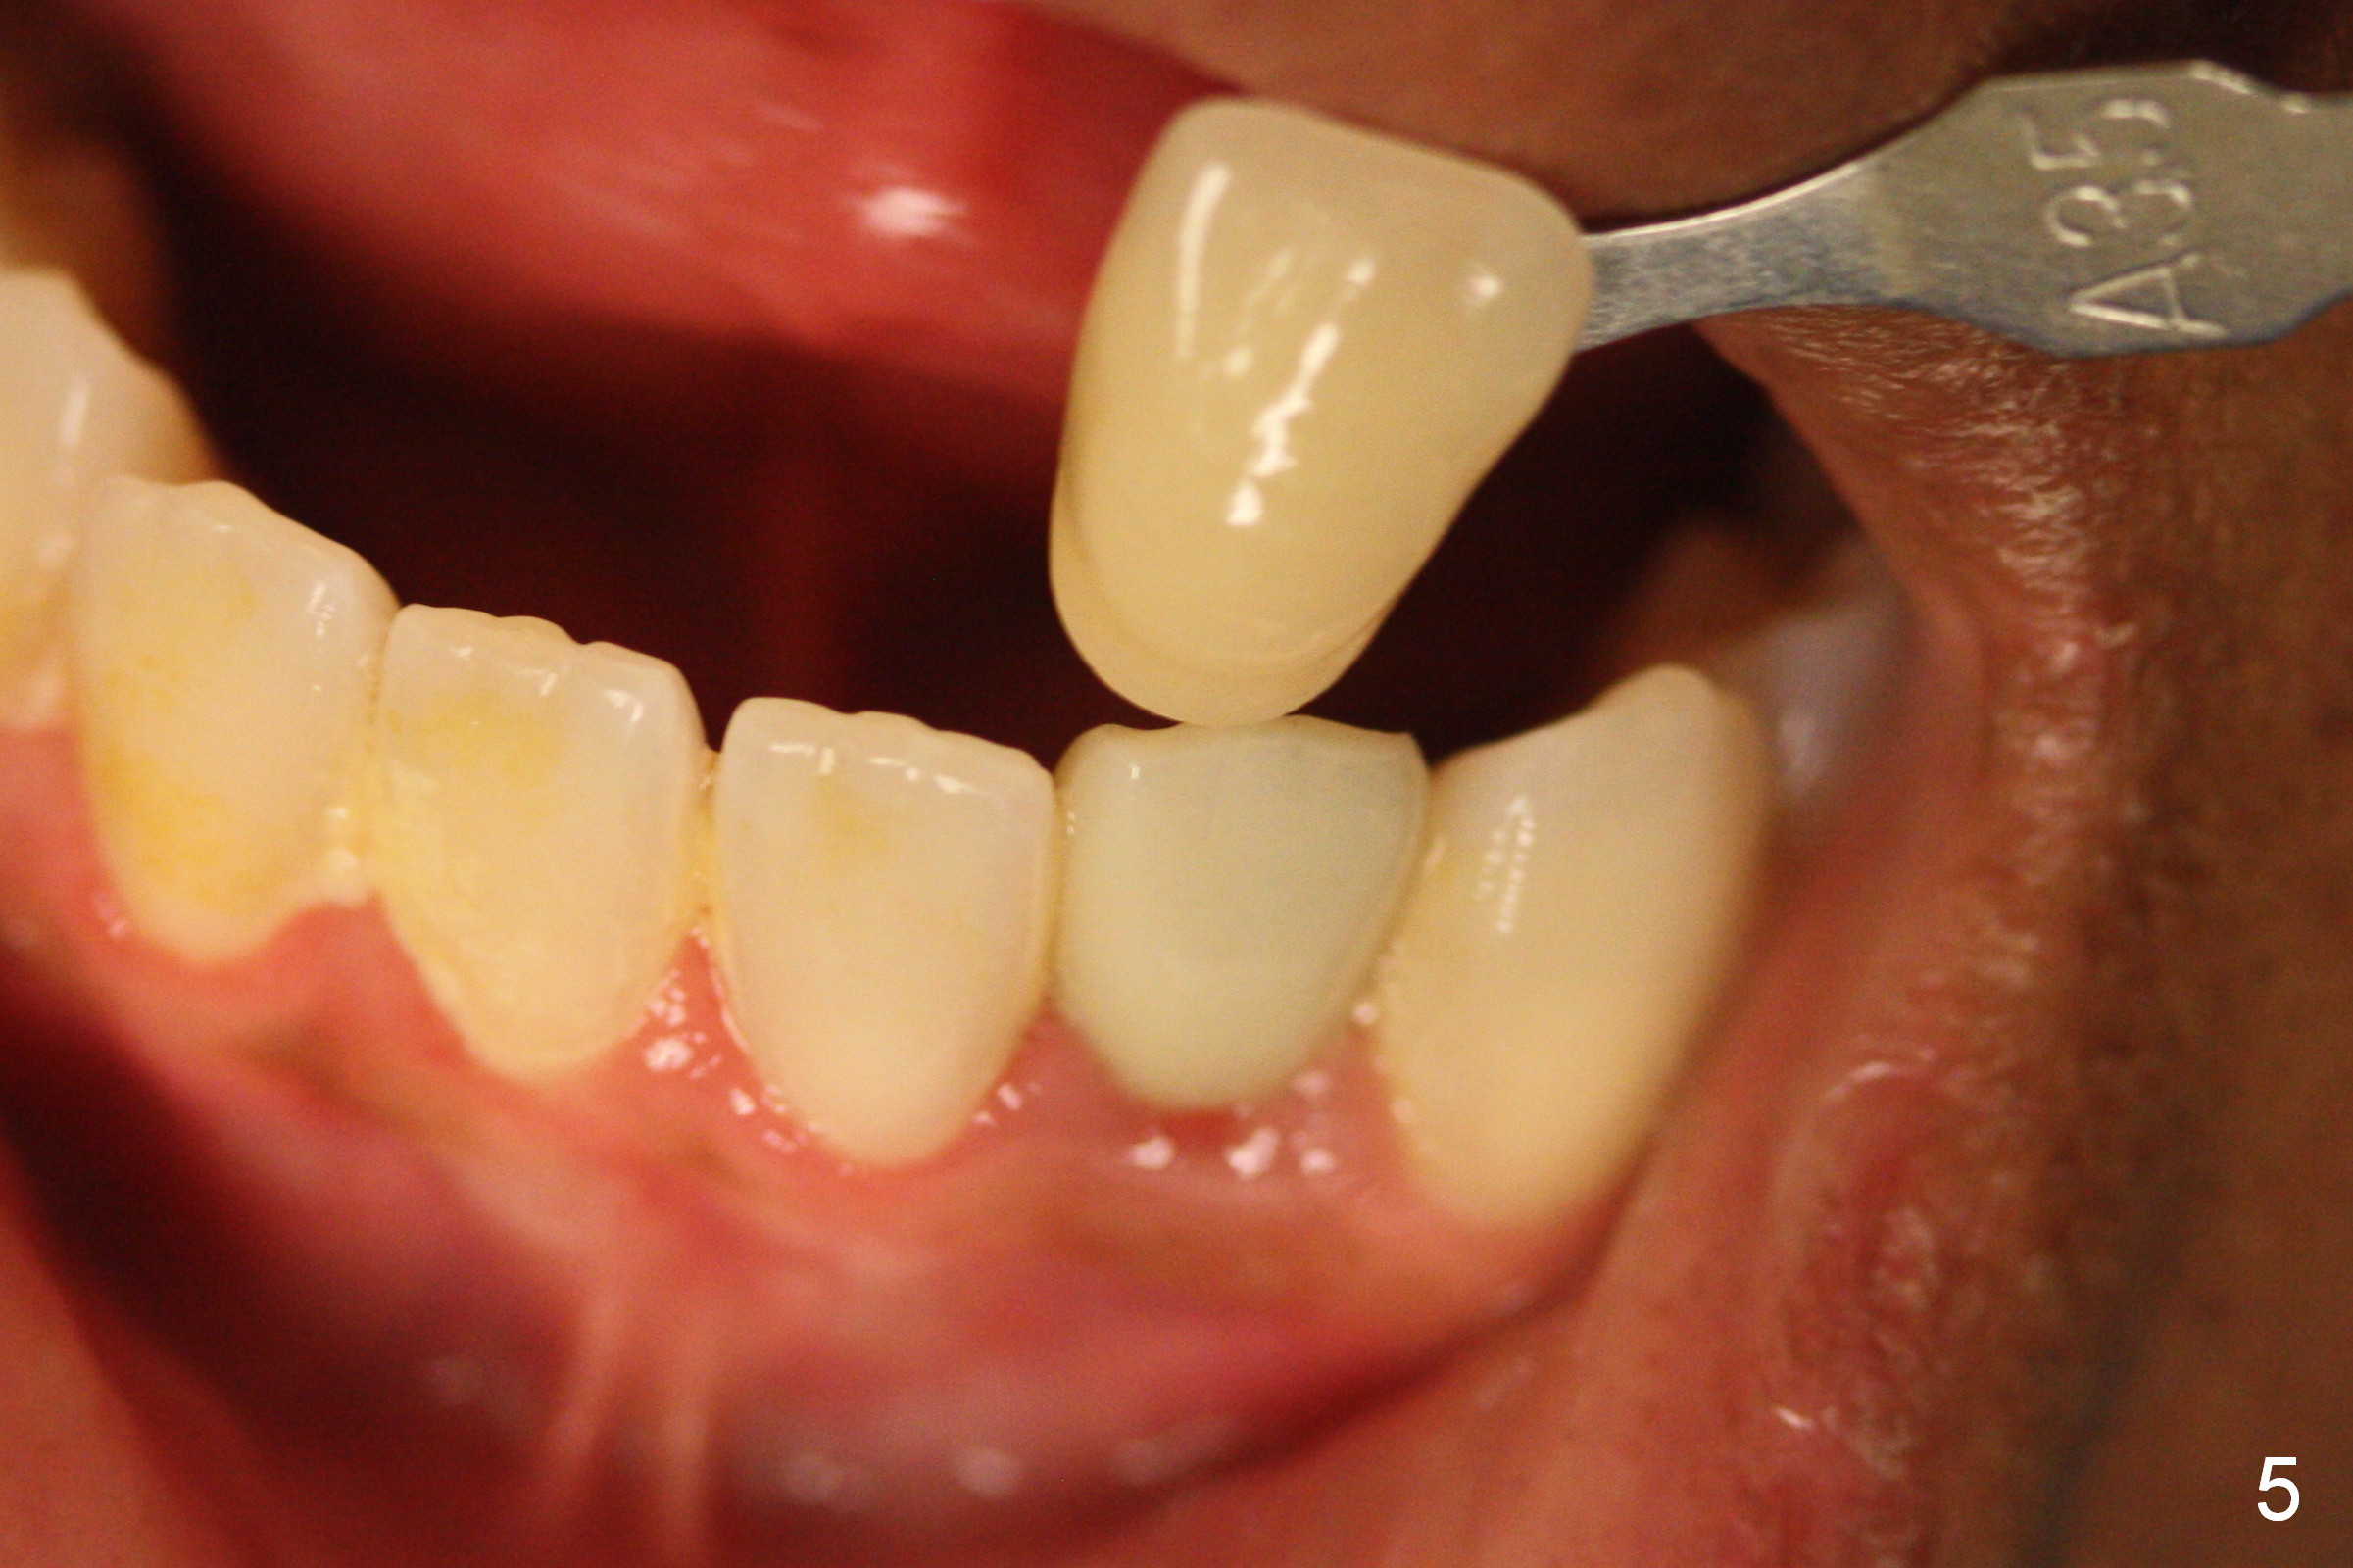

Suggestions for #23 implant crown redo (Fig.1, 2)

Make a new crown less transparent than the previous one (Fig.3). Can you block inside the crown to take care of the metal shade of the abutment/implant?

The original shade is A 2.5 (enclosed in the case).

Choose a shade a little darker and more yellowish (Fig.4-7 before

cleaning; Fig.9-11 after cleaning). It

appears that there is a change in shade of crown over the time.

Can you choose a Zirconia block that has the closest shade?

Do not stain or paint the crown.